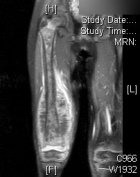

M.D. - 5 year old female with right thigh pain for one month, her parents have noticed swelling in her thigh over the past week, she began limping a few days ago and now is reluctant to bear weight on her right leg